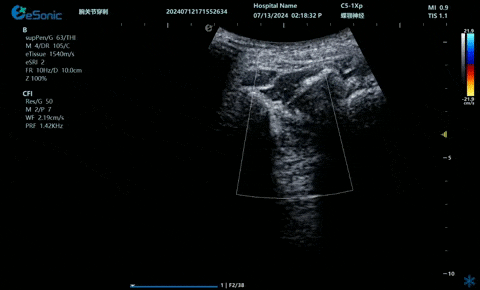

03

超声引导硬膜外麻醉-小等号

管内麻醉